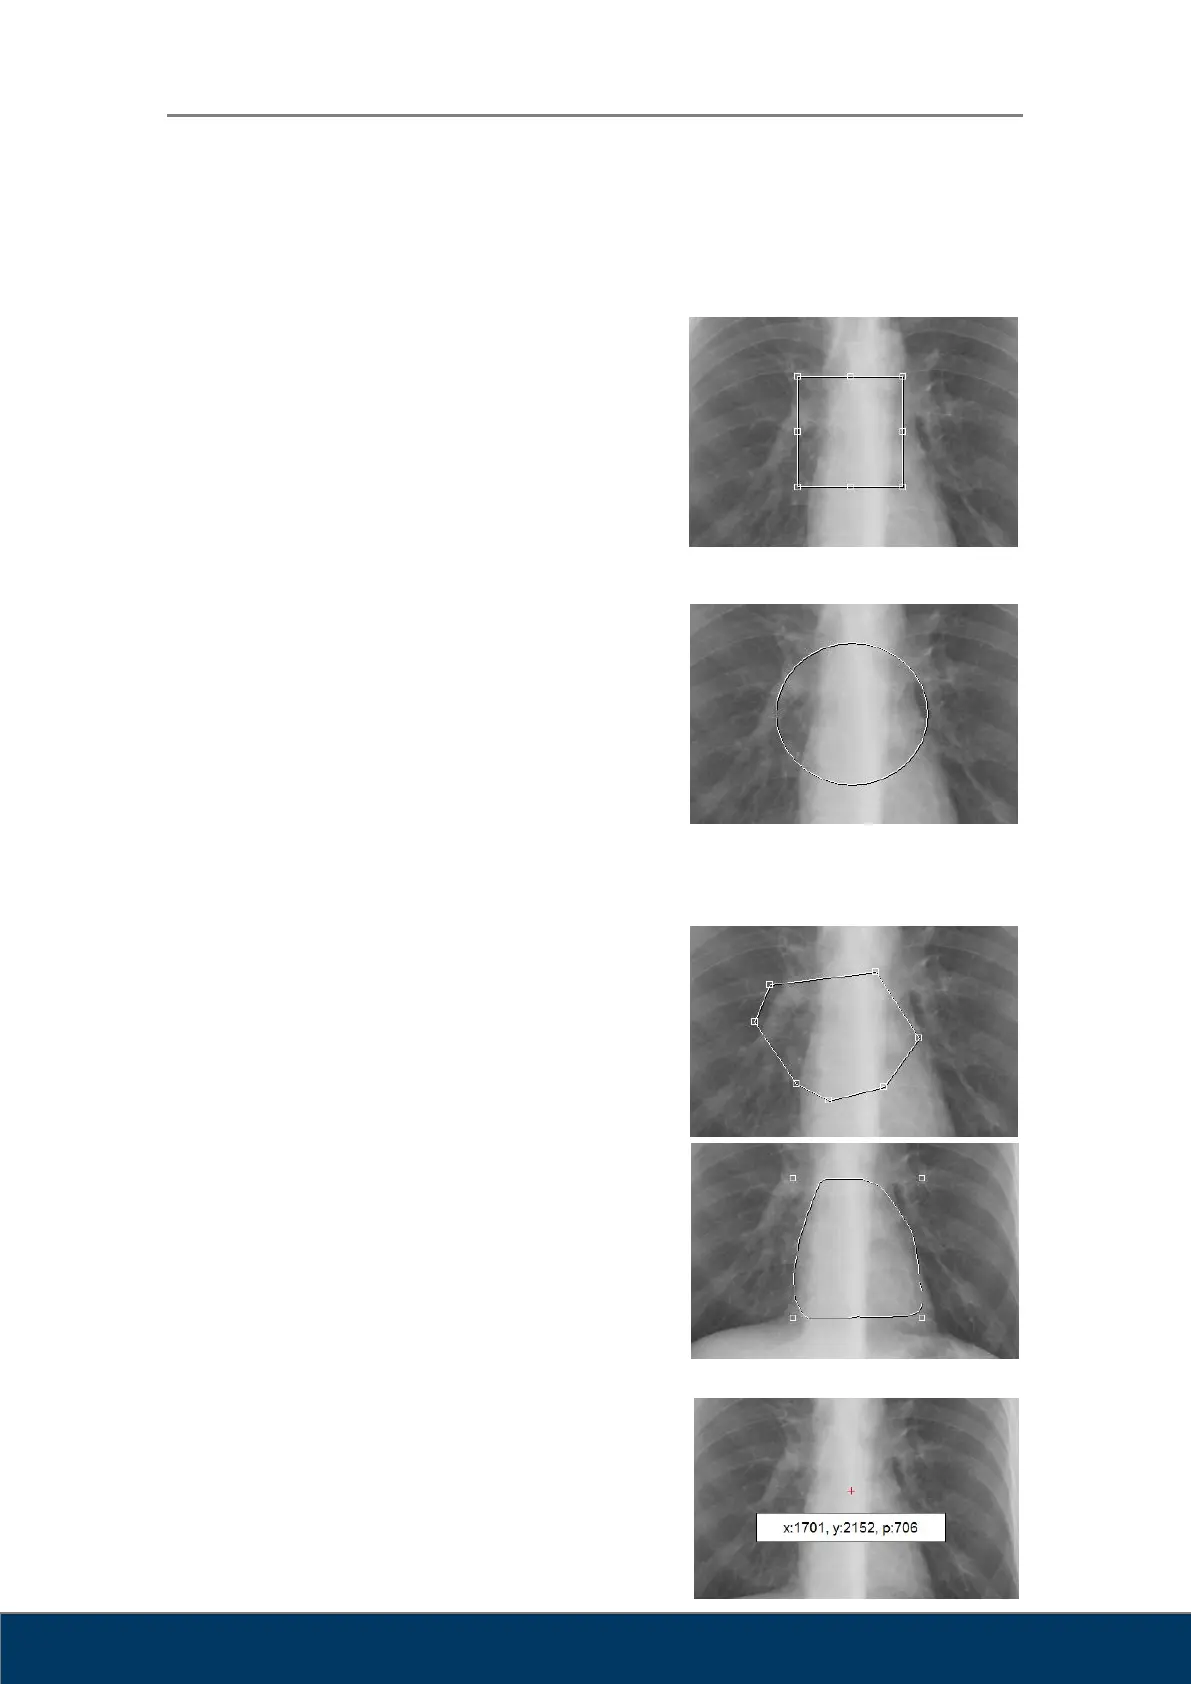

Rectangle: Draws a rectangle. Click the mouse at

the desired position of the upper left corner of the

rectangle, and then drag the mouse to the desired

position of the lower right corner of the rectangle

and release the mouse button. Click on an area

within the rectangle to move it. Drag the control

points to resize the rectangle.

Ellipse: Draws an ellipse. Click the mouse at the

desired position where the top and left-most point

of the ellipse would intersect, drag the mouse

toward the bottom right and release the mouse

after reaching a desired size and shape. Click on

an area within the ellipse to move it. Drag the

control points to resize the ellipse.

Draws a polygon. A control point is added every

time you click the mouse. Double-click when you

are done drawing the polygon. Click on an area

within the polygon to move it. Drag the control

points to change the corners of the polygon.

Creates a free draw selection. Click and drag the

mouse to the desired shape. Release the mouse

when you are done drawing. You can click inside

the selection to move the free draw selection.

Measures pixel value. Click and drag the mouse

and the coordinates (x, y) and pixel values (p) of

the pixel at the cursor position will be displayed on